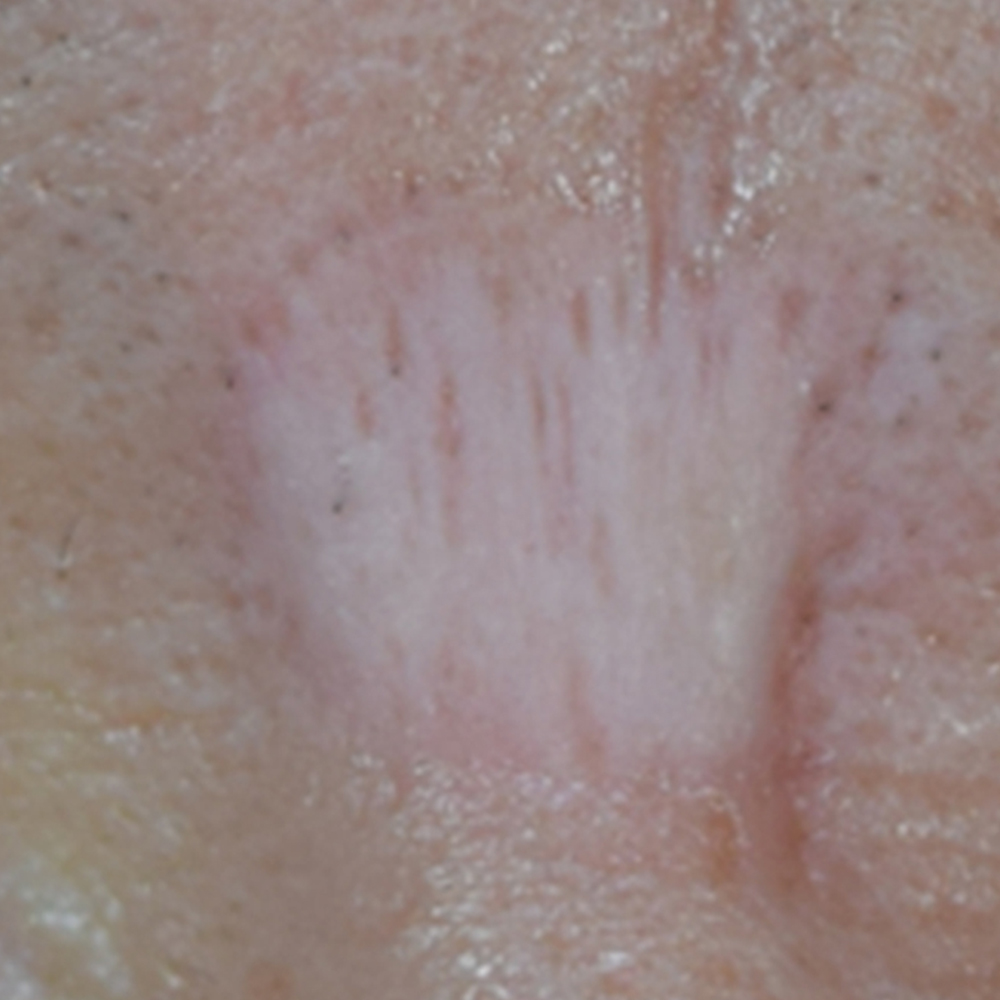

미간 흉터 레이저 치료 후

3개월이 경과한 시점의 모습.

치료는 약 3개월간 주기적으로 진행되었습니다.

초기에는 흉터의 단단한 질감이 조금씩 부드러워지면서 주변 피부와의 경계가 덜 도드라지기 시작했고, 이후에는 피부 톤의 차이가 줄어들며 자연스럽게 주변 피부와 어우러졌는데요.

시술 전에는 미간 중앙에 넓고 하얀 흉터가 뚜렷하게 자리 잡아, 정면에서 보았을 때 가장 먼저 눈에 띄는 상태였는데요.

그러나 시술 후에는 흉터 부위가 차츰 평탄해지고 색이 주변 피부와 비슷해지면서, 이전처럼 크게 눈에 띄지는 않는 모습이고요.